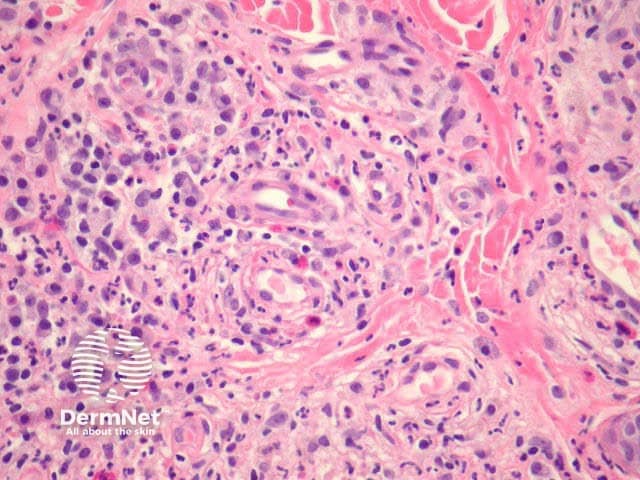

In erythema elevatum diutinum, there is sparing of the papillary and periadnexal dermis (Figures 1, 2). Vascular infiltration in the upper and mid-dermis with predominant neutrophils and fewer lymphocytes, eosinophils and plasma cells (Figures 3, 4, 5). Leucocytoclasia is commonly seen in fresh lesions (Figure 5). Later lesions develop sclerosis with plasma cells and residual foci of leukocytoclastic vasculitis. Sclerosis may be striking and have a storiform pattern (Figures 1, 4).

Figure 3